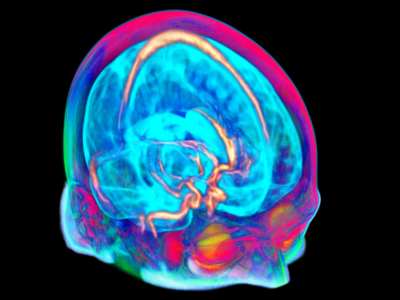

No 10 | Tractographie du cervelet